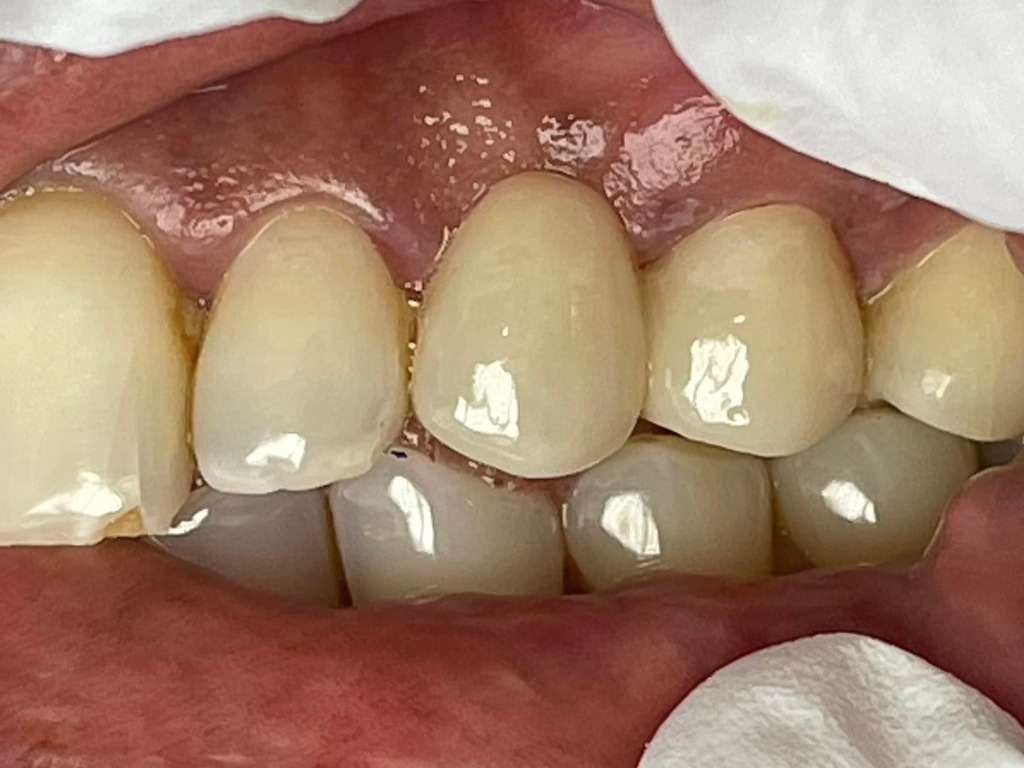

Case Study: Dental Bridges

Generate some text here.